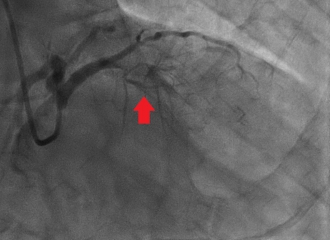

治療の一例

急性心筋梗塞の患者さん。左前下行枝の閉塞を認める(矢印)